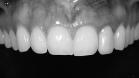

Ein Zahnimplantat ist eine künstliche Zahnwurzel aus Reintitan, die dauerhaft in den Kieferknochen eingesetzt wird. Durch den Prozess der Osseointegration verwächst das Implantat fest mit dem Knochen und bildet eine stabile Basis für Zahnersatz wie Kronen, Brücken oder Prothesen.